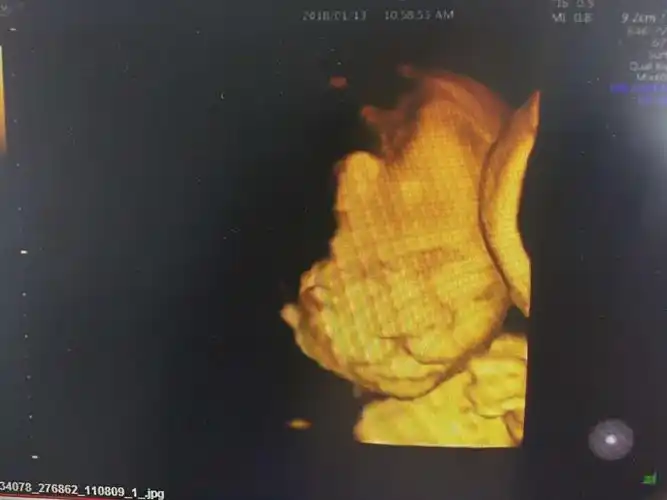

四维兔唇图片

四维照片宝宝这样算兔唇吗

大家帮忙看一下是兔唇吗?

遗憾!安真四维彩超筛查出一例胎宝宝"兔唇"

前两天做的四维,四维图上看起来正常,可是放大的照片看起来像兔唇,问

是唇裂吗?有出生结果

四维查出胎儿唇裂,为所有孕妈敲响警钟!

请帮忙看下四维彩超,是兔唇吗?很是担心!